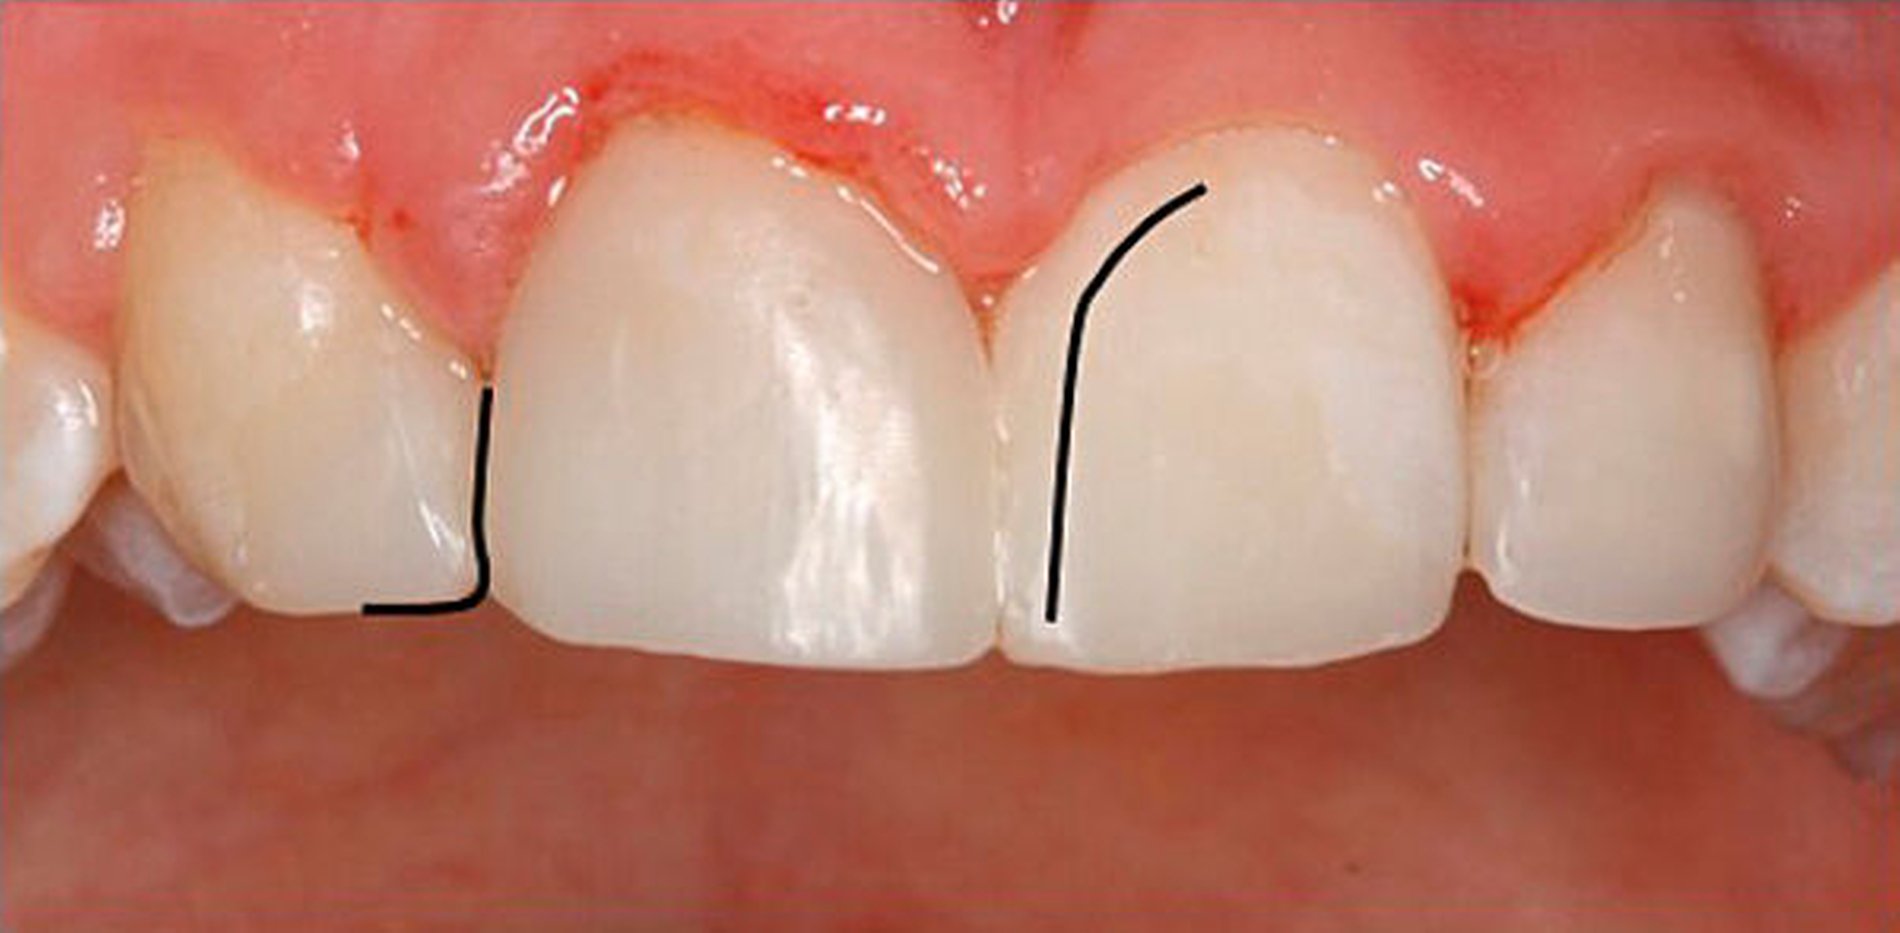

Die Rekonstruktion von Zähnen mit Komposit ermöglicht eine direkte und maximal zahnerhaltende Therapie, bei der die Zahnhartsubstanz nicht oder nur minimal im Sinne einer Anschrägung abgetragen werden muss. Im Vergleich zur Rekonstruktion mit keramischen Veneers muss dabei in der Regel wesentlich mehr Zahnhartsubstanz geopfert werden, um die nötigen Keramikschichtstärken einhalten zu können. Reparaturen, Farb- und Formanpassungen lassen sich mit der Komposittechnik im Vergleich zu Keramikrestaurationen immer wieder anpassen. Insbesondere bei jungen Patienten im Wachstum ist dies von Vorteil, um bei Veränderungen der Gingivaverhältnisse die rekonstruierten Zähne ihren Nachbarzähnen anzupassen (Verschluss schwarzer Dreiecke, zervikale Ausformungen).

In beiden Falldarstellungen wurden diese Bedingungen eingehalten. Eine Besonderheit stellt die Kombination von kieferorthopädischem Lückenschluss und Autotransplantation im zweiten Fall dar. Hier war vor der Rekonstruktion mittels Kompositaufbau eine Bewegung des Transplantats und der rechten Seitenzahnreihe erforderlich. Beides gestaltete sich ohne Probleme und sollte auch beim Verlust mehrerer Schneidezähne bedacht werden. Der Lückenschluss im Unterkiefer nach Keimentnahme konnte mithilfe skelettaler Verankerung ebenfalls reibungslos erfolgen. Es sollte jedoch wie beim kieferorthopädischen Lückenschluss die Anlage der dritten Molaren in der verkürzten Zahnreihe geprüft werden, um für den zweiten Molaren des Gegenkiefers einen Antagonisten zu haben. Ziel des Beitrags war es, die Autotransplantation nach Frontzahnverlust und Aplasie ins differenzialdiagnostische und -therapeutische Spektrum als gleichberechtigte Variante einzubeziehen.